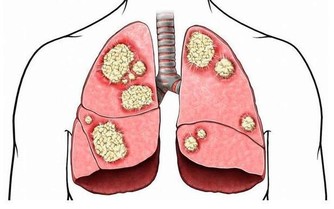

維生素A可修復肝能力,遏止和抑止肝臟中癌細胞的增生。